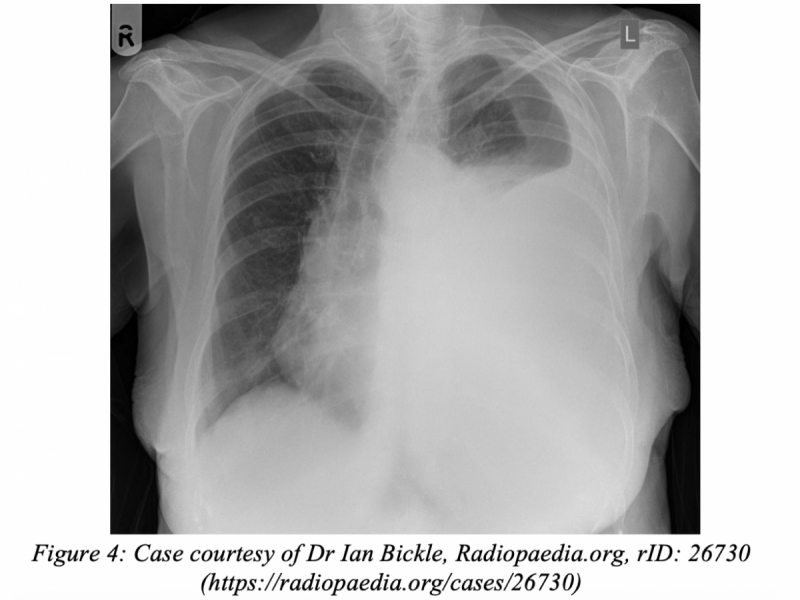

A 45-year-old female with a history of ovarian cancer

What's the Diagnosis? By Dr. Loran Hatch

40 yo F presents to the ED w/ 12 hours of GI symptoms. She